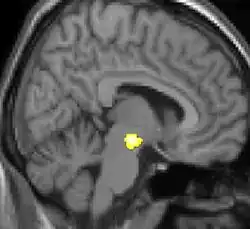

| Voxel-based morphometry shows brain area structural differences. | ||

Positron emission tomography (PET) scans indicate the brain areas which are activated during attack only, compared to pain free periods. These pictures show brain areas that are active during pain in yellow/orange color (called "pain matrix"). The area in the center (in all three views) is activated only during cluster headaches. The bottom row voxel-based morphometry shows structural brain differences between individuals with and without CH; only a portion of the hypothalamus is different.[37]